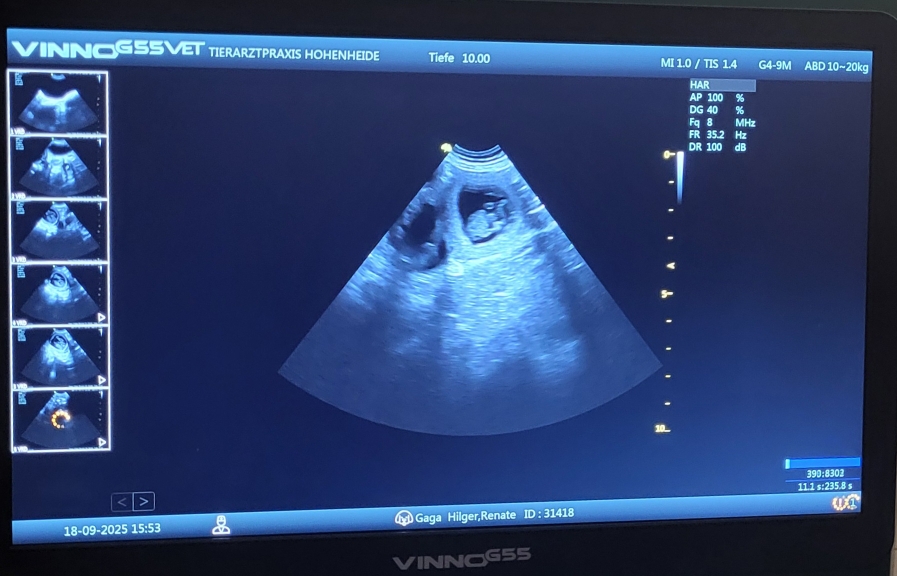

Wir waren heute beim Ultraschall und, wie wir vermutet haben, ist Gaga tragend. Im Gegensatz zu ihrem ersten Wurf scheint es ein großer Wurf zu werden.